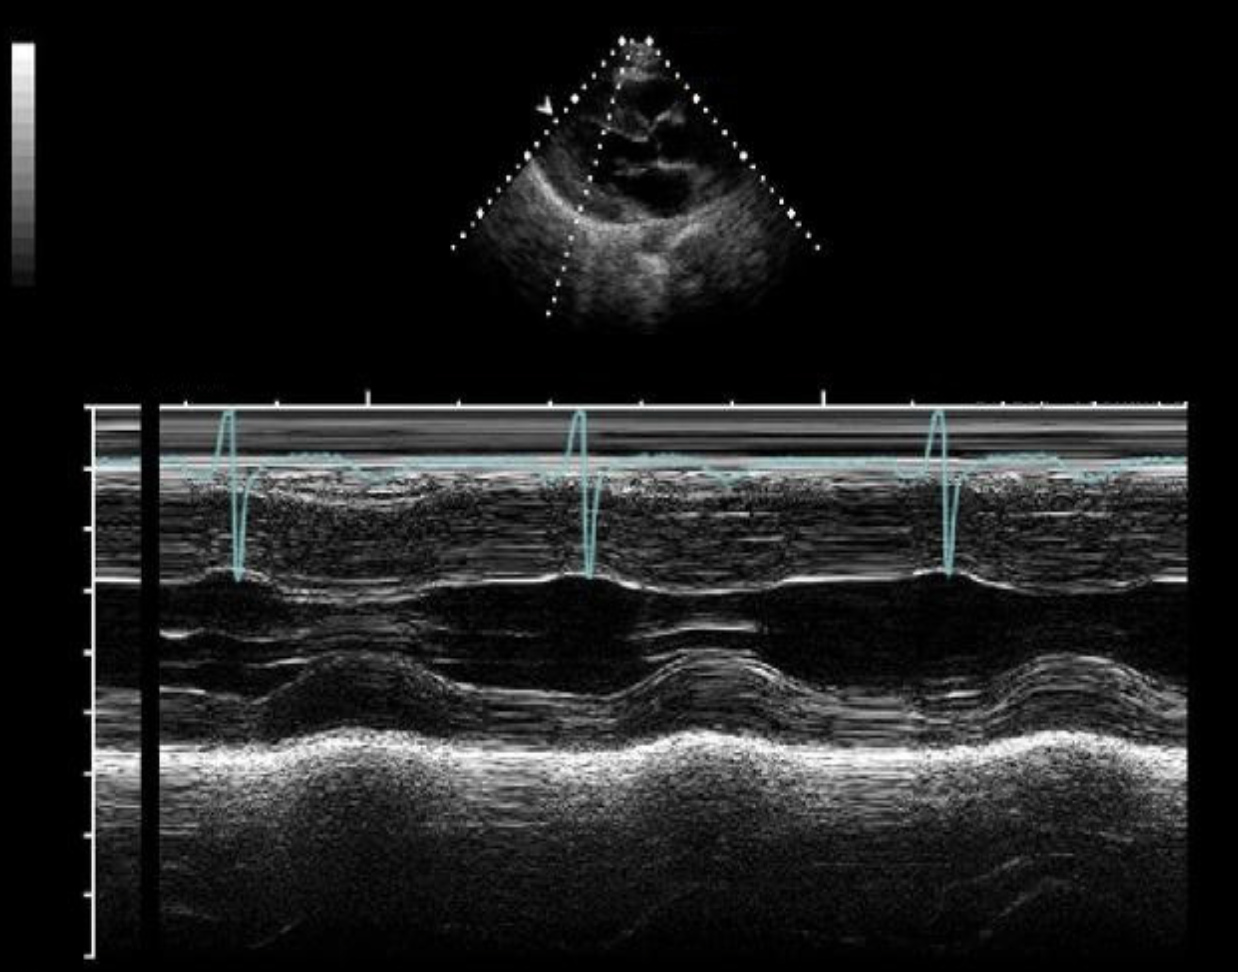

The m-mode tracing demonstrates which of the following?

HCM

The m-mode tracing is consistent with which of the following cardiac abnormalities?

Cardiac tamponade